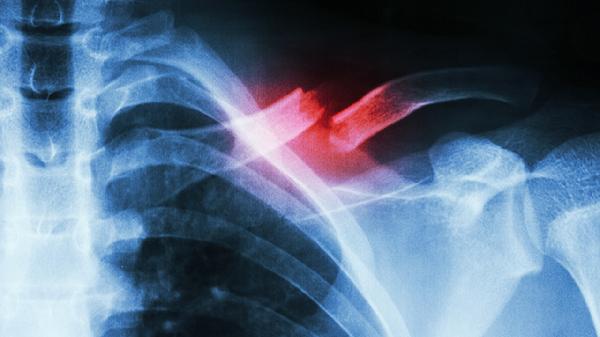

三、图像辨识

黑白超声显示组织结构,彩色部分标记血流方向与速度。红色代表朝向探头流动的血液,蓝色标示背离探头的血流,色彩饱和度与流速呈正比。医生通过测量病灶大小、观察边界清晰度、评估血流信号等参数进行诊断。